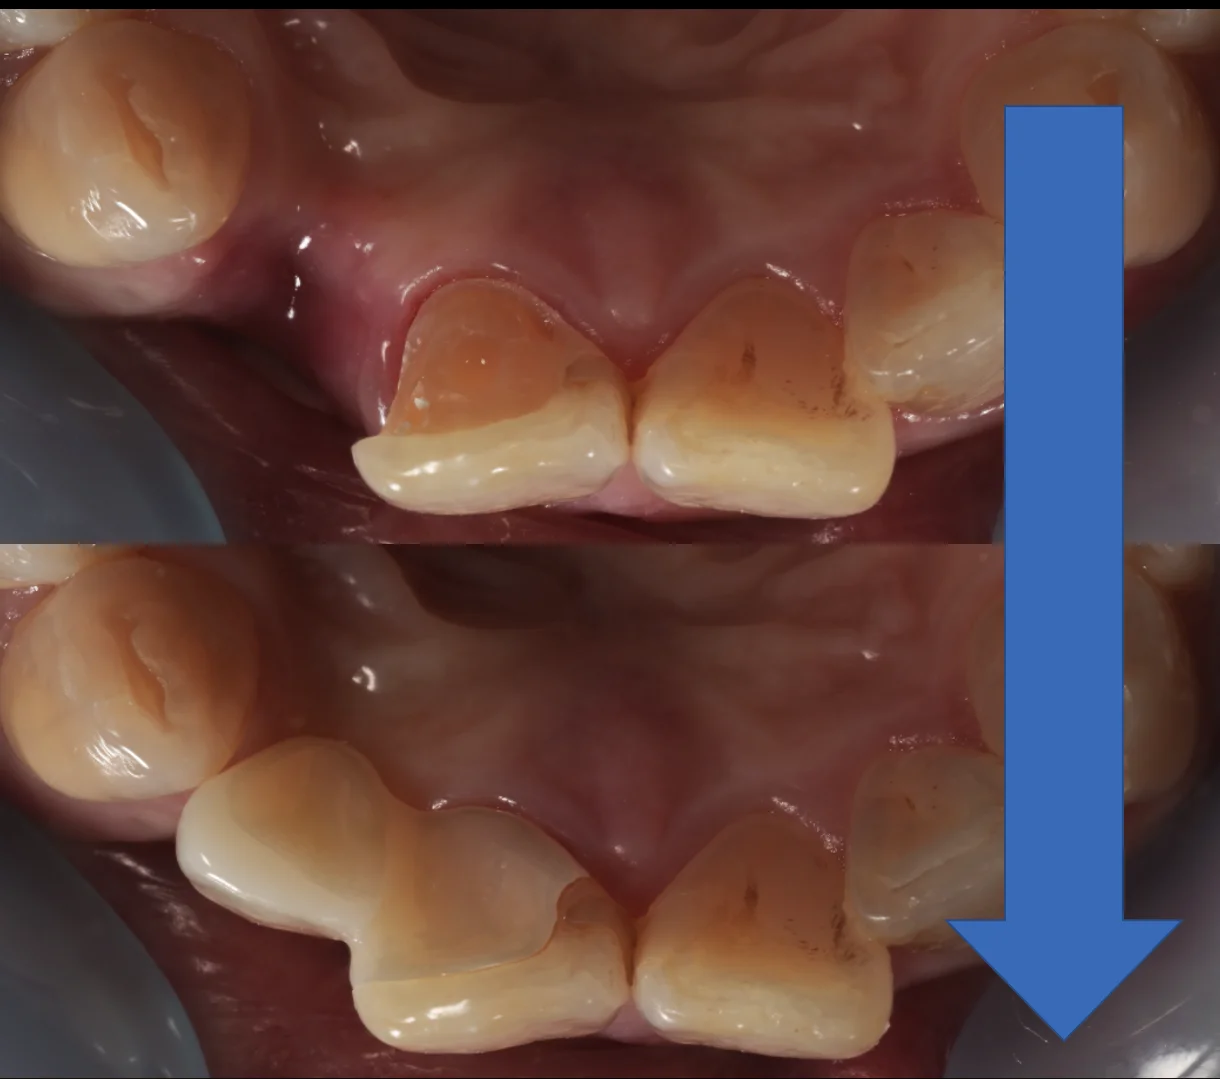

噛む面からの術前術後です。